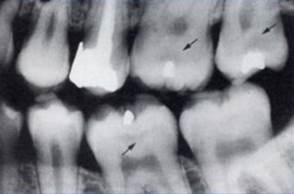

Bitewing

-рентгенография

(BWRh, Raper, 1920г)

применяется для диагностики скрытого кариеса на апроксимальных поверхностях зубов.

Регистрируются симметричные участки обоих челюстей с отображением коронок зубов и альвеолярного края верхней и нижней челюсти. Пленки размером 2,7 на 5,4 - специальный пленкодержатель с накусочной площадкой

Рис. 11. Рентгеновский снимок